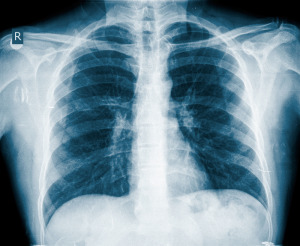

La pneumonie est un facteur de risque de la maladie du cœur

Selon une étude publiée récemment dans le Journal of the American Medical Association , l’hospitalisation en raison d’une pneumonie est un important facteur de risque de la maladie cardiovasculaire (MCV) chez les personnes d’âge moyen et âgées qui n’ont pas d’antécédent de maladie du cœur.